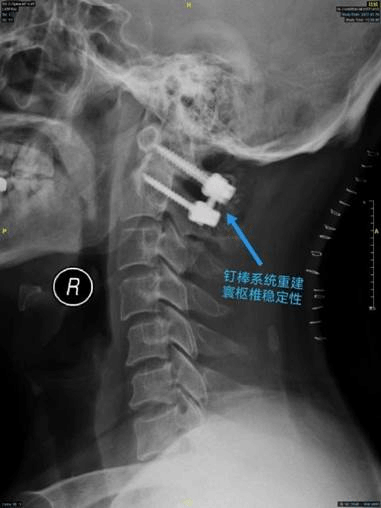

术后x线侧位片

术中,在麻醉科、手术室等科室的密切配合下,赵伟教授团队根据术前三维CT结果设计的置钉方向,精准的置入了寰椎侧块螺钉和枢椎椎弓根螺钉,通过提拉撑开技术实现寰枢椎脱位的解剖复位、彻底的恢复了患者脊柱的稳定性。术后当日,患者麻醉清醒后即感到四肢肌力部分恢复,双下肢可以屈膝离床。随着术后一系列的治疗,张先生上肢的力量也在逐渐恢复,并可以站立行走。